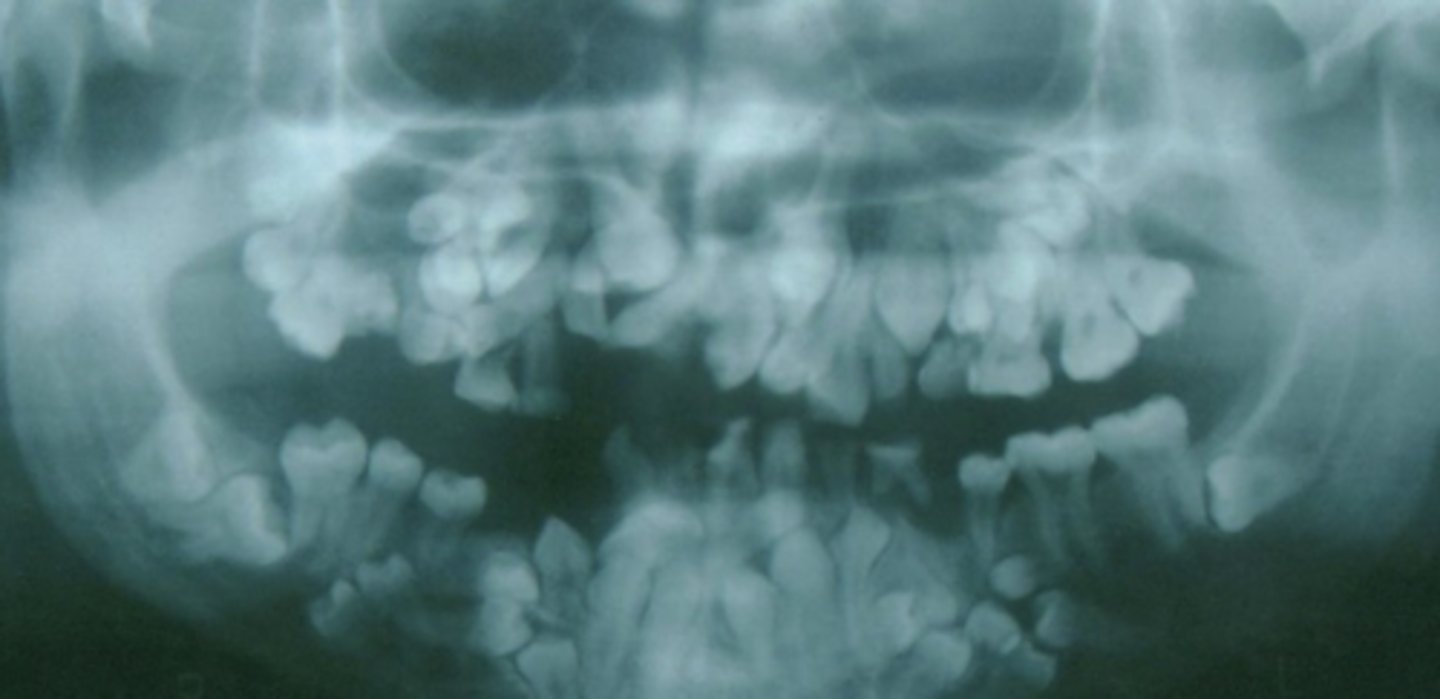

Dentinogenesis imperfecta

- Discolored teeth (yellow/brown/grey)

- Lack of enamel, exposed dentin

- Bulbous crowns

- Obliterated pulp chamber

- Short roots